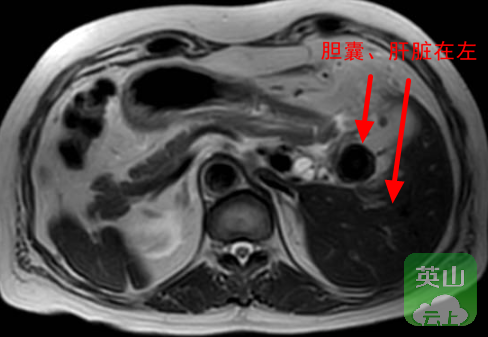

“镜面人”即医学上的“全内脏反位”,是一种发生概率仅为百万分之一的先天性解剖变异。此类患者的全部脏器位置与正常人呈镜像对称,心脏位于右侧,肝脏位于左侧,脾脏位于右侧,仿佛生活在“镜像世界”之中。

依托与武汉大学中南医院的紧密型学科共建机制,医院迅速启动了疑难病例多学科协作流程。术前,两地专家团队基于CT、MRCP等影像资料,进行了细致的三维重建与分析,共同制定了详细的手术方案与应急预案。术中,面对腹腔镜视野下“肝脏在左、胆囊在左”的镜像画面,英山县医共体总医院(县人民医院)胸外肝胆外科手术团队凭借前期扎实的预案准备与对解剖结构的深刻理解,在共建学科专家的现场支持下,迅速适应视角转换,精准辨识并分离反位的胆囊管及周围血管。整个手术过程流畅有序,仅用时60余分钟便顺利完成,术中出血控制良好,患者安全返回病房。